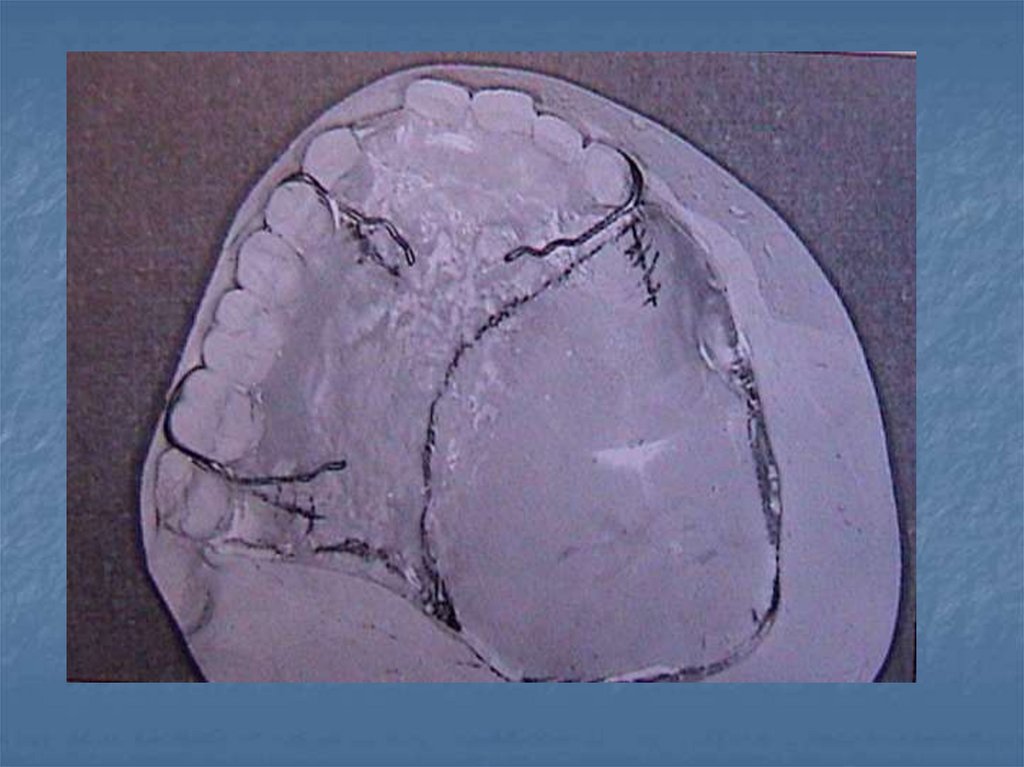

premaksillayı da içine

almıştır. Eğer varsa

kalan dişler bir hat

üzerindedir. Defekt